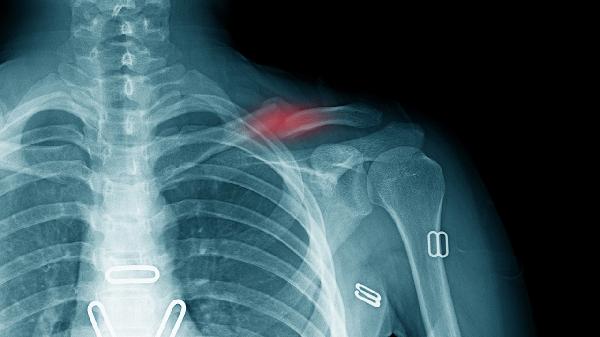

右锁骨骨折后一般4-6周可恢复自主进食能力,实际恢复时间受到骨折类型、固定方式、康复训练、年龄及营养状况等因素影响。

线性骨折对位良好者约4周可尝试用健侧手辅助进食,粉碎性骨折或伴有移位需6周以上。稳定性骨折早期可通过调整进食姿势减轻患侧负担,不稳定骨折需严格制动至骨痂形成。

八字绷带固定者需维持肩关节制动3-4周,期间建议使用吸管或斜面餐具。手术内固定患者2周后可在支具保护下进行抓握训练,逐步过渡到持勺动作。